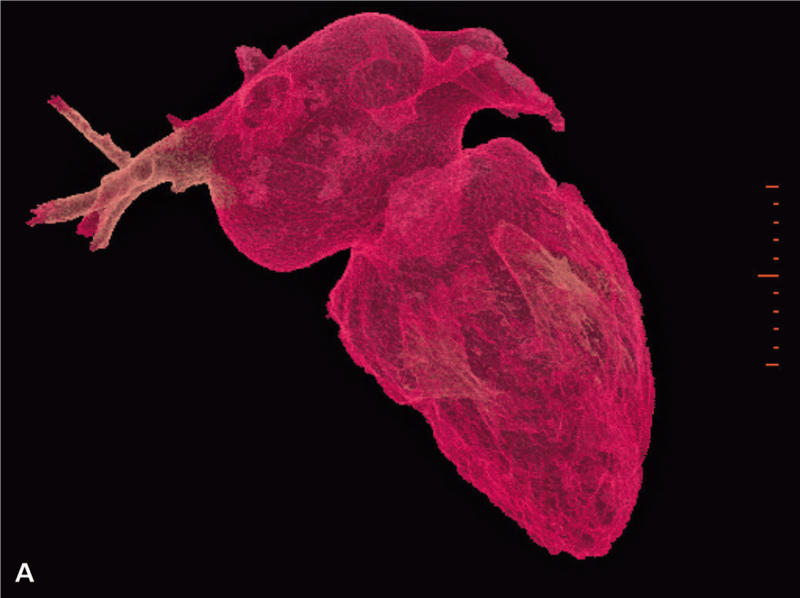

Po operacji wykonano kontrolne badanie TK serca, w którym nie stwierdzono zmian ogniskowych i zagęszczeń zapalnych w uwidocznionym miąższu płucnym. Przełyk oraz pozostałe uwidocznione badaniem struktury śródpiersia również były bez zmian. Uwidocznione węzły chłonne nie były powiększone. Badanie wykazało stan po plastyce przedsionka lewego oraz wszczepieniu sztucznego pierścienia w pierścień zastawki mitralnej. Objętość przedsionka po zabiegu wynosiła 129 cm3 (przed zabiegiem 186 cm3) (ryc. 1A, B, 2A, B).

RYCINA 2. Rekonstrukcja objętościowa (VR transparent) lewego przedsionka. [A] Przed operacją. [B] Po operacji.

Objętość późnorozkurczowa LK przed zabiegiem wynosiła 295 cm3, a po zabiegu 222 cm3 (ryc. 3A, B, 4A, B).

RYCINA 4. Rekonstrukcja objętościowa (VR transparent) jam serca lewego. [A] Przed operacją. [B] Po operacji.